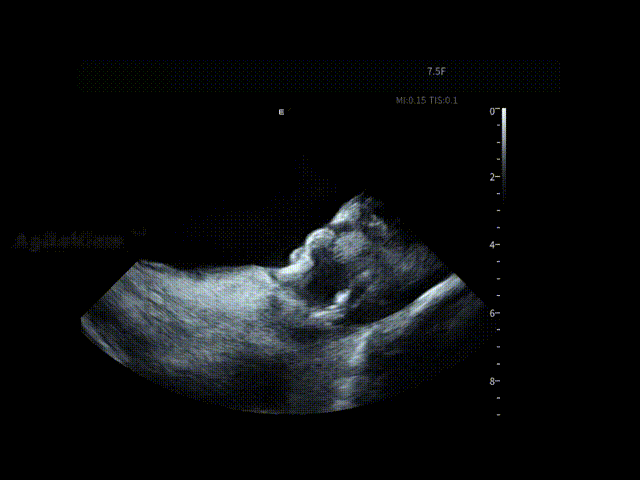

在消融手术开始前,邹操教授将ICE导管经股静脉穿刺进入右房进行术前筛查,为手术安全提供第一道影像保障。术者对左心房、左心耳及心包区域进行了系统性扫查,在导管消融前评估该患者不存在左房血栓情况,并进行术前心包监测。

AgileView™ ICE的高清实时超声成像使潜在风险在早期即可被发现与排除,让后续操作始终建立在“可视、可控”的安全基础之上,有效提升整体手术安全性。

术前心包-有明显积液